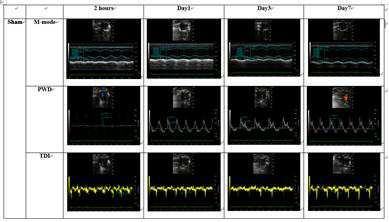

심혈관계 약물의 유효성에 대한 심초음파 평가 방법